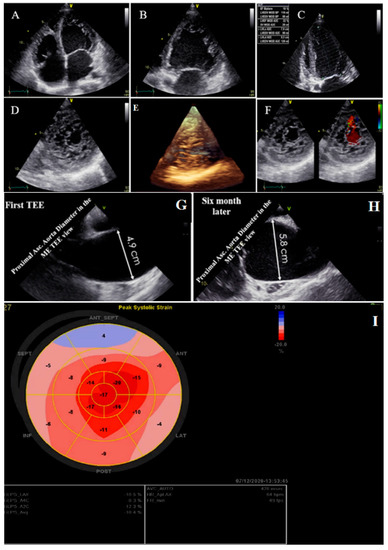

A 56-year-old retired military general was referred with dyspnea on exertion for 3 months, which became worse over time. He had no underlying disease or cardiovascular risk factor. On physical examination, he had tachycardia and tachypnea and used accessory muscles of respiration, and on cardiac auscultation, an audible left-sided S3 gallop with “tic-tac” heart sounds was detected. On ECG, he had sinus tachycardia, low voltage QRS complex, and poor R progression in the precordial leads. TTE showed NCLV with severe global hypokinesia (LVEF = 16%), dilated aortic root and proximal ascending aorta (diameter = 49 mm; indexed = 23 mm), and effacement, in addition to the presence of PFO. A genetic study showed mutations in the DSP (e.3857_3859del: p.1286_1287del.), TTN (c.C80492T: p. P26831L), and DSC2 (c.A1886G:p.N629S) genes. A 6-month follow-up TTE showed a fast-growing aortic root aneurysm that reached 58 mm (indexed = 28 mm), although the patient was receiving beta-blockers and had no clinical symptoms. STE showed impaired myocardial performance with relative apical sparing and coronary angiography with the left ventricle and aortic root cineangiography showed dilated LV with remarkable recesses and dilated aortic root (6.25 cm) (Figure 2). The patient was scheduled for a valve-sparing aortic root replacement surgery (David procedure). The perioperative and postoperative TEE showed normal functioning native aortic valve with minimal aortic insufficiency and no aortic stenosis. At the follow-up visit, the patient had no clinical symptoms related to heart failure. The family members refused genetic study because of the high costs of the test (not covered by the insurance).

Figure 2.

Two- and three-dimensional transthoracic echocardiographic views of case #2: (A–C); left ventricular apical four and two-chamber views. (D,E); Apical SAX view, illustrating hypertrabeculated apical portions in addition to deep intertrabecular recesses and reduced left ventricular ejection fraction (LVEF = 16%, calculated by Simpson’s method). (F); Color Doppler echocardiography, showing evidence of direct blood flow from the ventricular cavity into deep intertrabecular recesses. (G,H); Transesophageal echocardiographic findings of baseline (left) and 6 months later (right); follow-up test showed fast-growing aortic root that reached 5.8 cm. (I); Speckle tracking echocardiographic findings, compatible with myocardial performance impairment plus relative apical sparing (GLS = −10.4%).